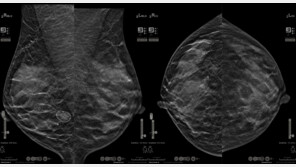

홀로직 코리아는 30일 AI 진단 보조 소프트웨어 Genius AI 2.0 신제품의 도입 초기 테스트 단계에서 유방암 의심 병변을 조기에 포착하며, AI 기술의 진단 정확도와 임상적 가능성을 확인했다고 밝혔다.고려대학교 구로병원 영상의학과에서 진행된 유방 촬영 장비 신제품 테스트 중 …